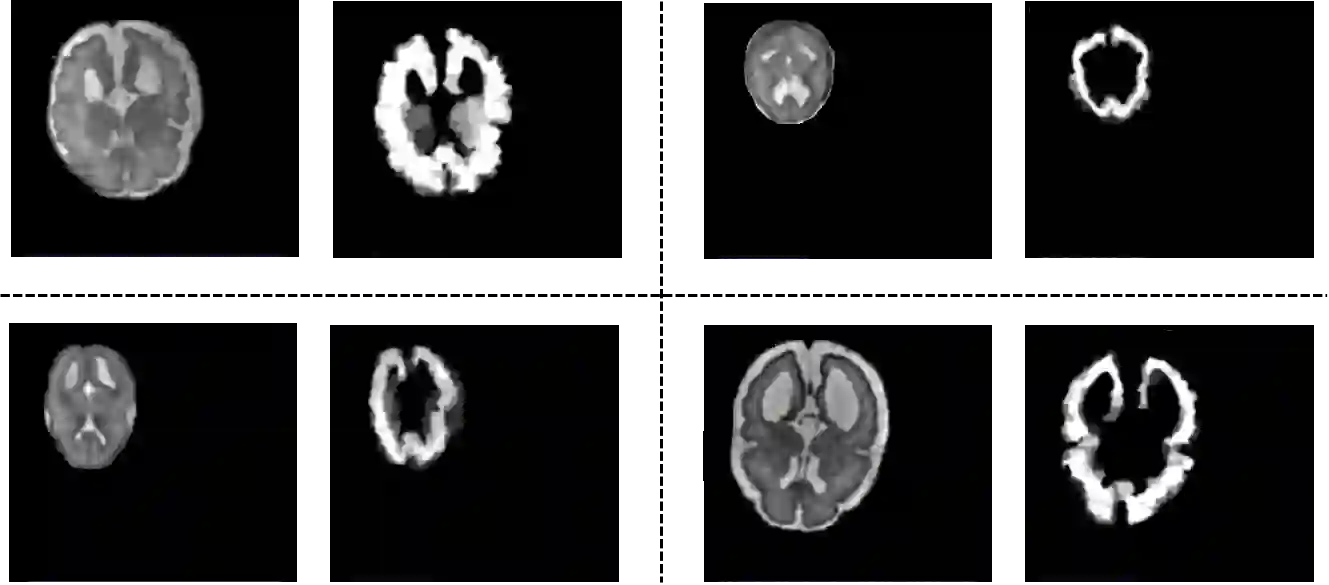

Lesions or organ boundaries visible through medical imaging data are often ambiguous, thus resulting in significant variations in multi-reader delineations, i.e., the source of aleatoric uncertainty. In particular, quantifying the inter-observer variability of manual annotations with Magnetic Resonance (MR) Imaging data plays a crucial role in establishing a reference standard for various diagnosis and treatment tasks. Most segmentation methods, however, simply model a mapping from an image to its single segmentation map and do not take the disagreement of annotators into consideration. In order to account for inter-observer variability, without sacrificing accuracy, we propose a novel variational inference framework to model the distribution of plausible segmentation maps, given a specific MR image, which explicitly represents the multi-reader variability. Specifically, we resort to a latent vector to encode the multi-reader variability and counteract the inherent information loss in the imaging data. Then, we apply a variational autoencoder network and optimize its evidence lower bound (ELBO) to efficiently approximate the distribution of the segmentation map, given an MR image. Experimental results, carried out with the QUBIQ brain growth MRI segmentation datasets with seven annotators, demonstrate the effectiveness of our approach.